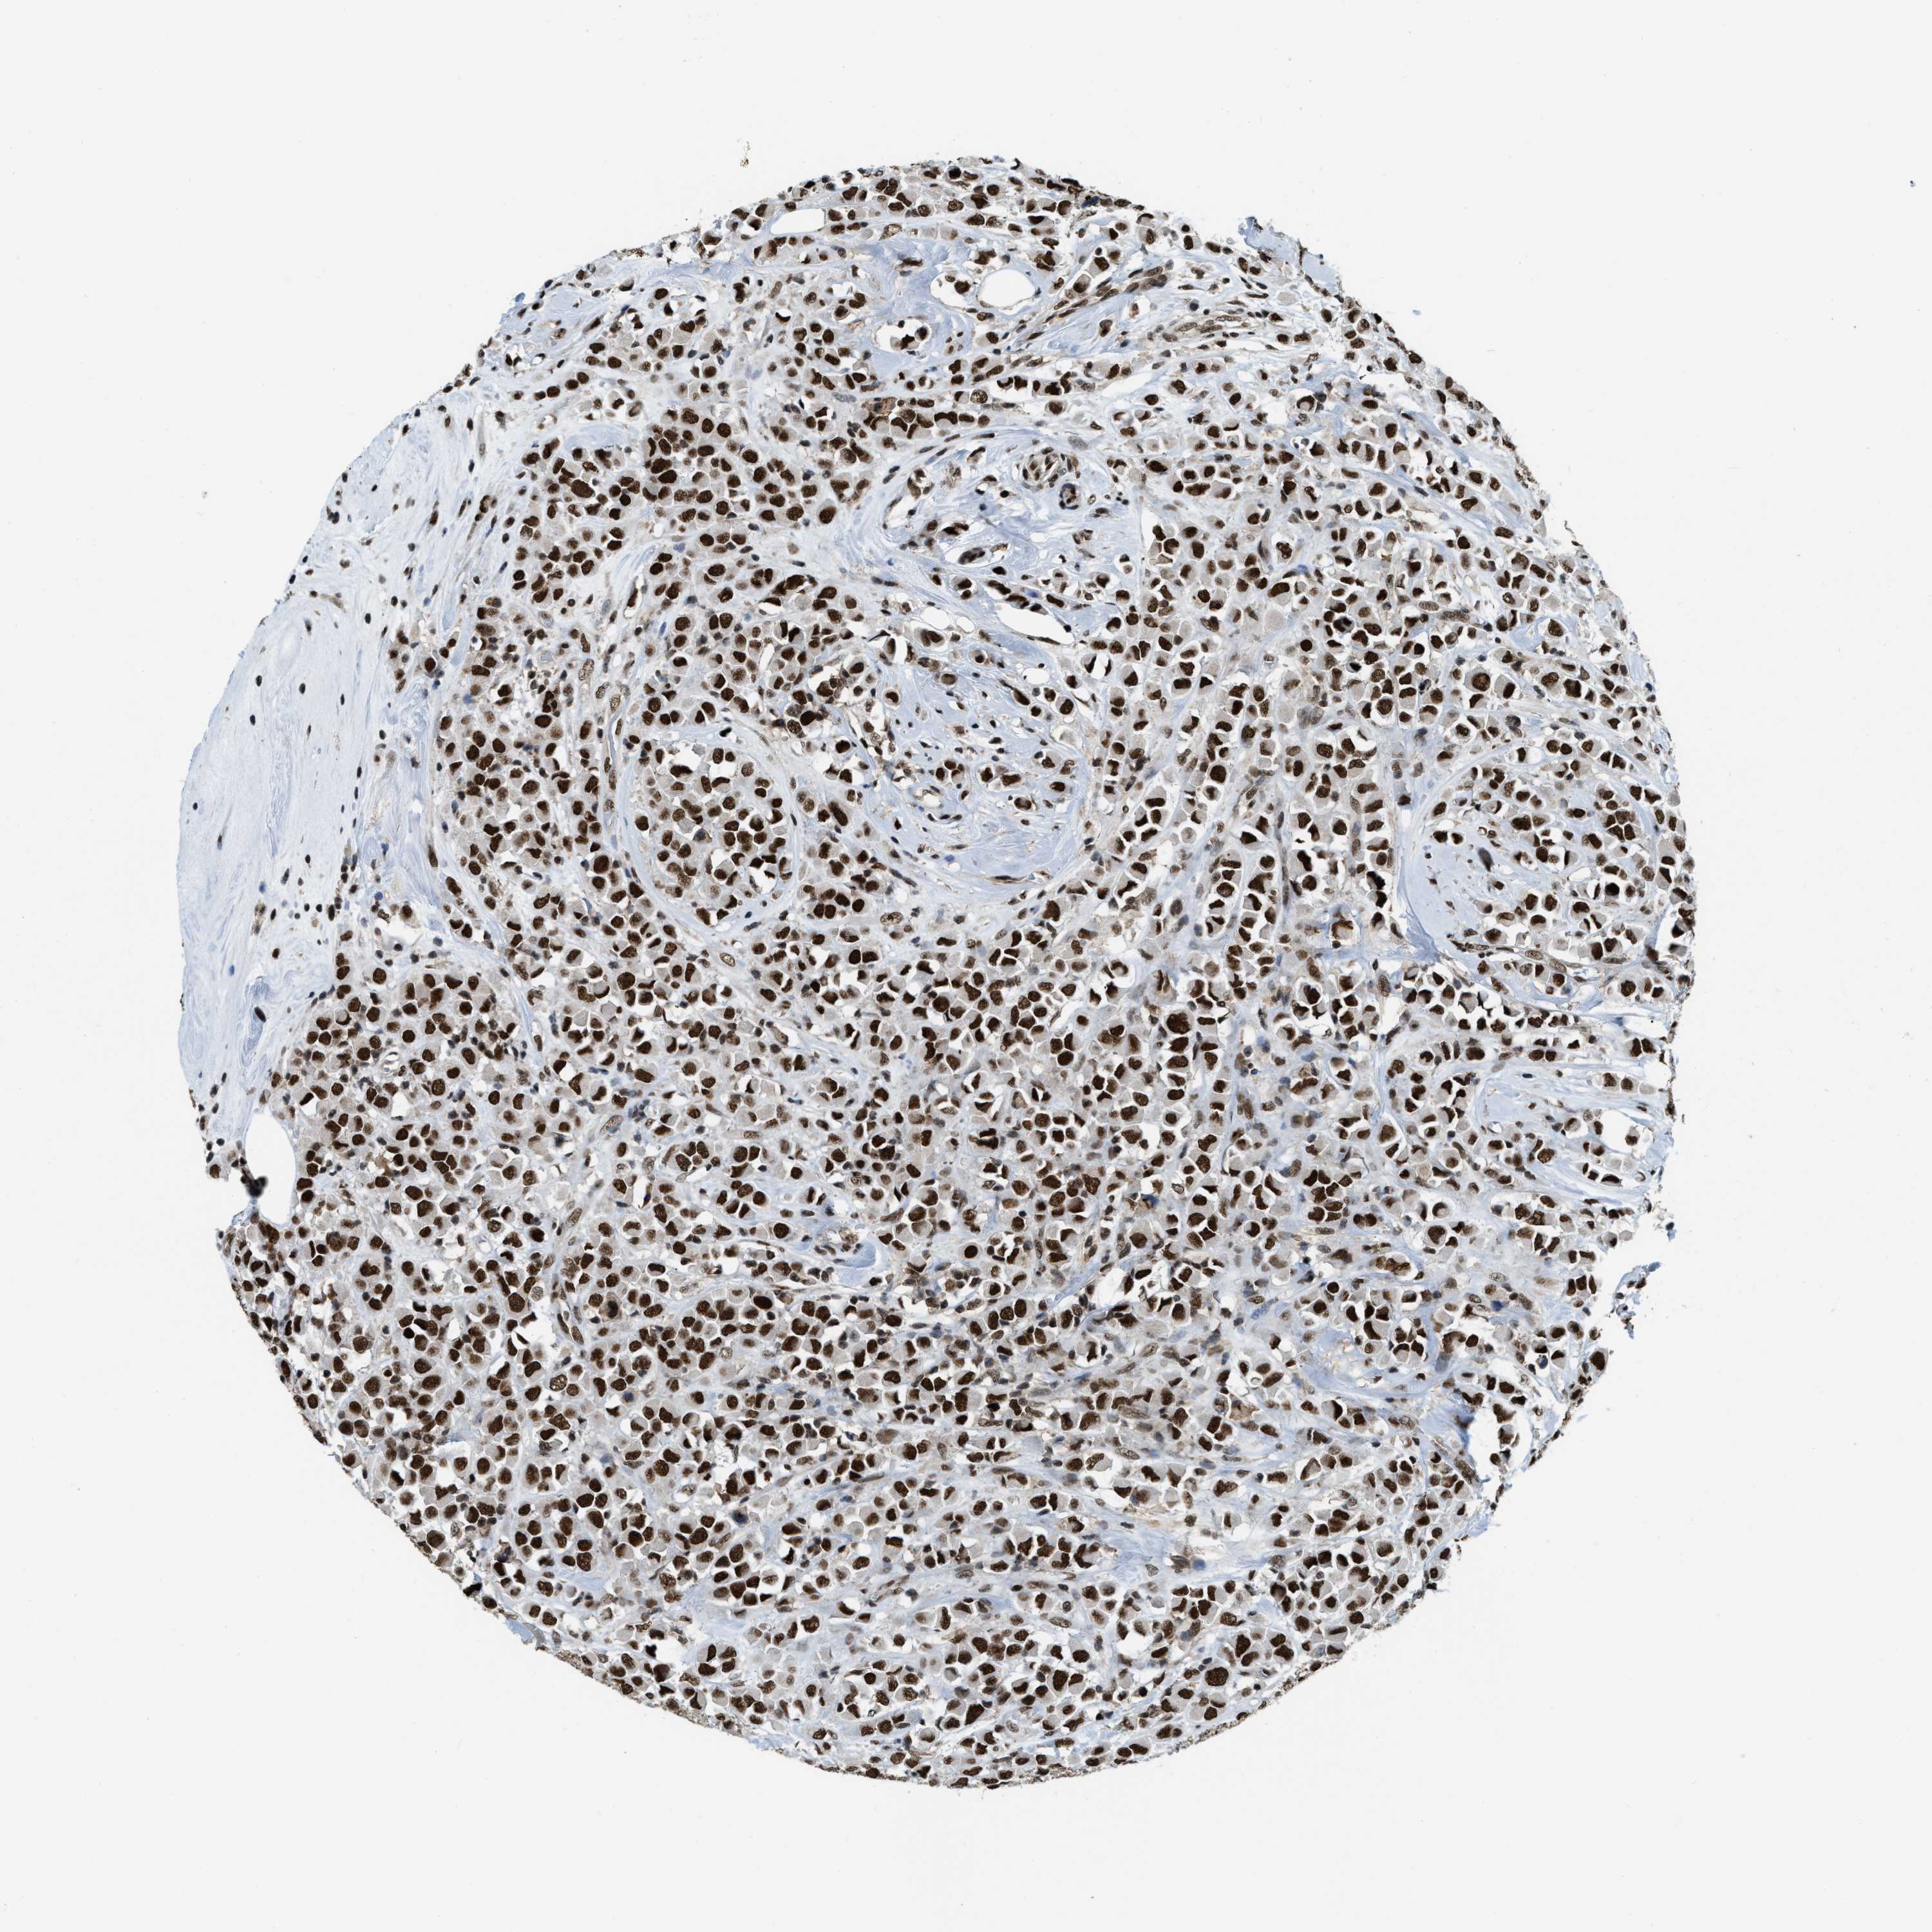

CANCER BREAST CANCER Show tissue menu

BRCA TCGA BRCA VALIDATION PROTEIN EXPRESSION

Breast cancer

Human cancer